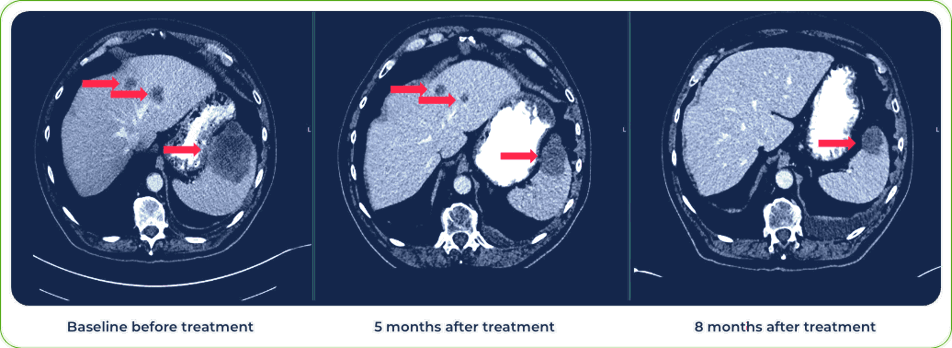

Diagnosis:

Stage IV metastatic melanoma

Single dose induced regression of large metastatic lesion in the liver